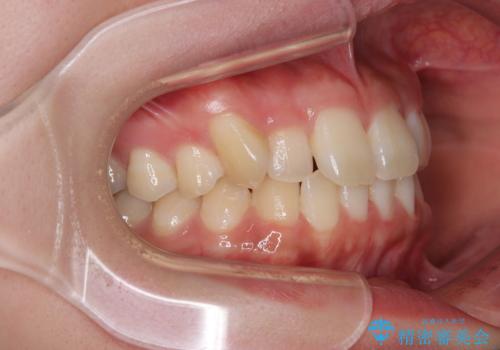

- 上下前歯のデコボコを気にして来院された患者様です。

僅か8ヶ月という短期間で、綺麗な歯列に仕上がりました。